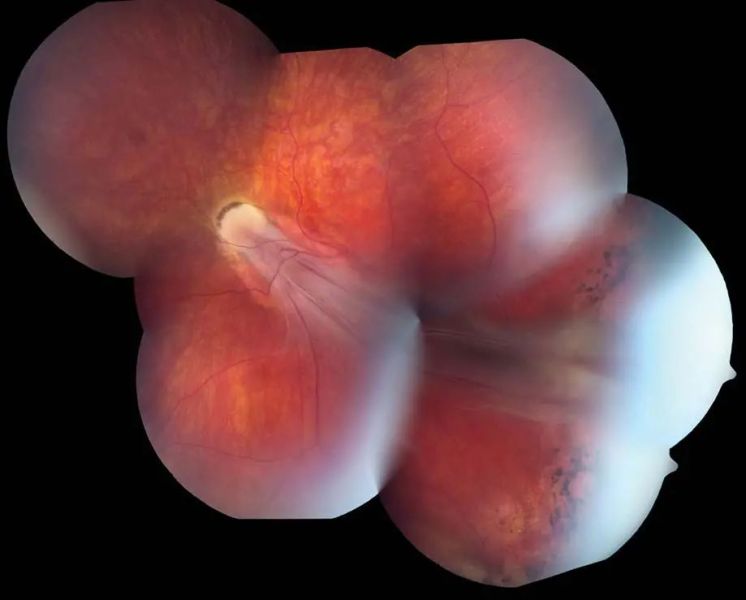

Retinopathy of Prematurity. Montage color fundus photograph from an adult who had untreated ROP as an infant, showing severe dragging of retinal vessels and a macular fold extending to the temporal periphery. Diffuse pigmentary changes are also visible. (Courtesy of Franco M. Recchia, MD.)